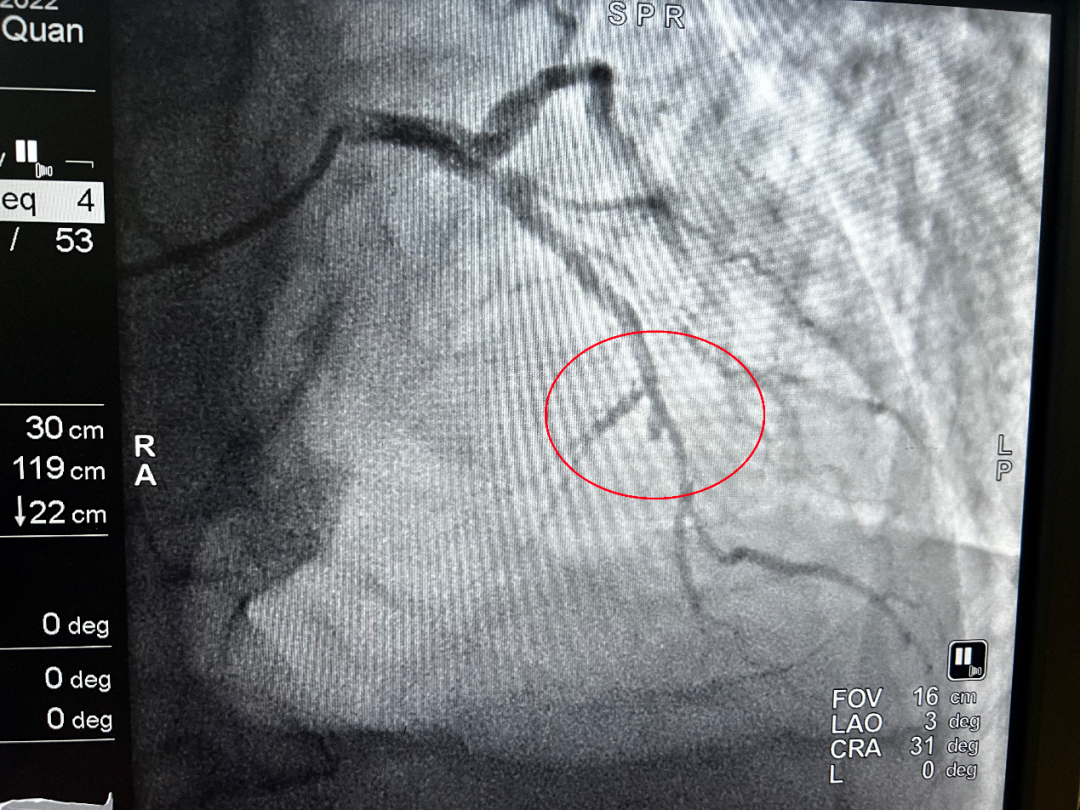

(介入前)

凌晨1點34分,導管室激活;1點38分,患者平車送入導管室;1點48分,穿刺成功;2點01分,導絲通過血管閉塞處……從王大爺首次醫(yī)療接觸到導絲通過,僅用時54分鐘。所有醫(yī)護人員繃緊神經(jīng),爭分奪秒,為患者開辟了一條脫離危險的綠色通道。術后,患者胸痛癥狀明顯緩解,轉危為安。